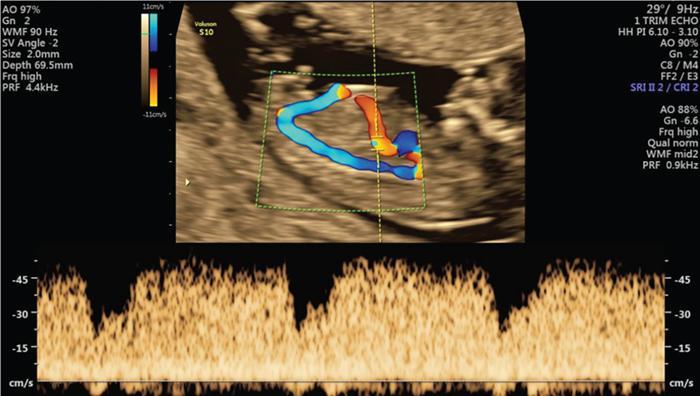

• In order to facilitate the passage of this blood through the liver, some of the sinusoids enlarge to create a direct passage connecting the left umbilical vein to the right hepatocardiac channel. This passage is called the ductus venosus (Fig. 9.6.6).

Image

Fig. 9.6.6 Ductus venosus: Classical triphasic waveform where the flow should be in the forward direction, directed to the heart.